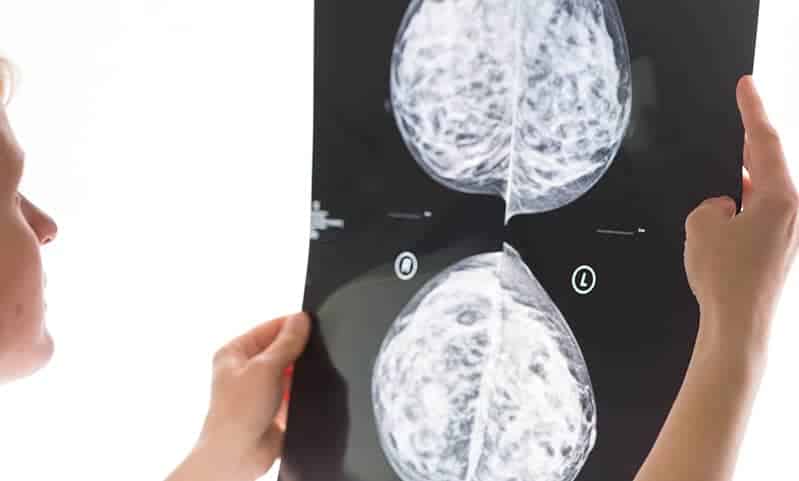

Eine aktuelle Studie festgestellt, dass Mammographien bei der Entdeckung von Brustkrebs bei Männern mit hohem Risiko erfolgreicher sind als bei Frauen mit durchschnittlichem Risiko.

Die Studie ergab, dass die Mammographie-Erkennungsrate für männlichen Brustkrebs besser war als die Erkennungsrate für weibliche Brustkrebs-Screenings, wobei 18 Fälle der Krankheit pro 1.000 männlicher Untersuchungen und nur fünf Fälle pro 1.000 weiblicher Untersuchungen entdeckt wurden.

Mediziner führen dies darauf zurück, dass die männliche Brust weniger dicht ist als die weibliche, wodurch Anomalien im Gewebe aufgrund fehlender Milchdrüsen und Milchgänge leichter zu erkennen sind.

Bei Frauen wird das Mammographie-Screening durch die größere Menge und Dichte des Brustgewebes behindert, das Krebsknötchen verdecken kann.

Männliches Brustgewebe besteht tendenziell aus mehr Fettgewebe, was eine bessere Visualisierung von Knötchen mit der Bildgebung ermöglicht.

Vor dieser Studie war sehr wenig über die potenziellen Vorteile oder Risiken der Mammographie bei Männern bekannt. Die Forschung legt nahe, dass die Mammographie bei Männern mit hohem Risiko ebenso wie bei Frauen als wirksames Screening-Instrument angesehen werden sollte.